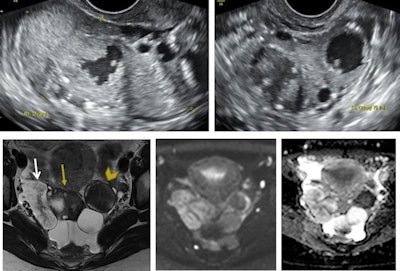

The eligibility criteria for ovarian carcinoma fertility-sparing treatment are the following:

- Malignant germ-cell tumors, malignant sex-cord stromal tumors, borderline ovarian tumors, and epithelial ovarian cancers (stage IA and unilateral inferior colliculus)

- No evidence of contralateral ovary involvement, and no evidence of pelvic or peritoneal extension

- Absence of lymph-node metastasis, and absence of distant metastasis